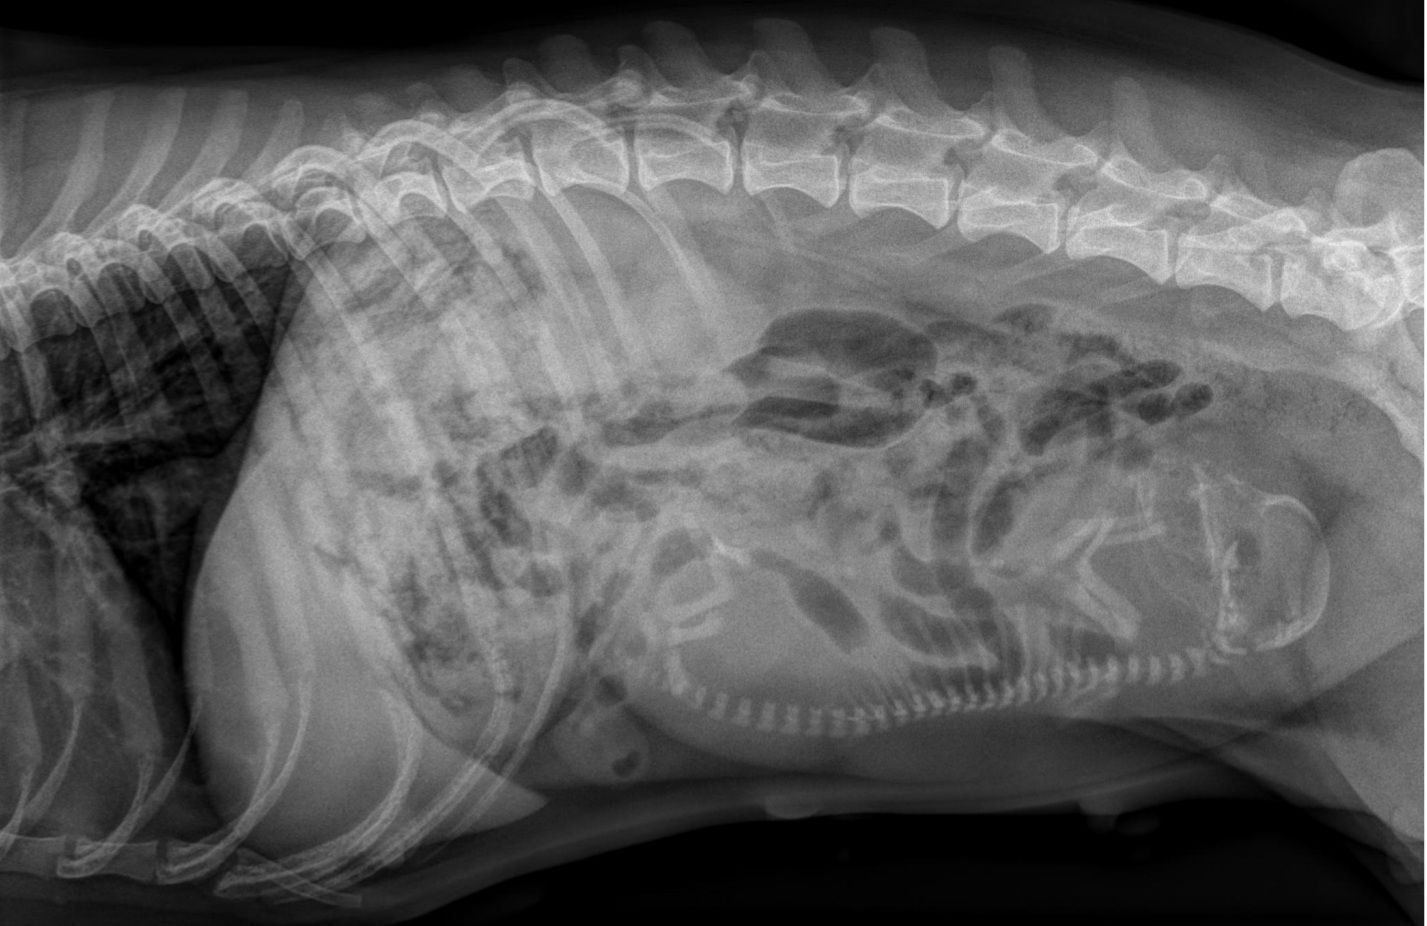

Es wurde leider nur ein Welpe gesichtet.

Am 28.06.2024 ist die kleine Aimée geboren. Ihr Geburtsgewicht ist sehr gut. Mutter und Baby sind wohlauf.